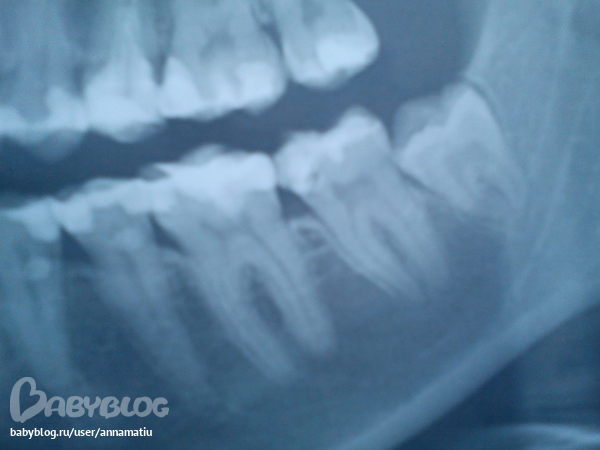

На снимке меня вот, что смутило

В 6 зубе пломба стоит пряяяяяям на роге пульпы, это может давать боль.

В 7 зубе смущает неоднородность пломбировочного материала.

На 7 снизу справа зубе киста!!!! Сделайте прицельный рентгеновский снимок, если там такая же картина- перелечивать зуб обязательно.

Горизонтальные стрелки указывают на возможный кариес на контактных поверхностях зуба.